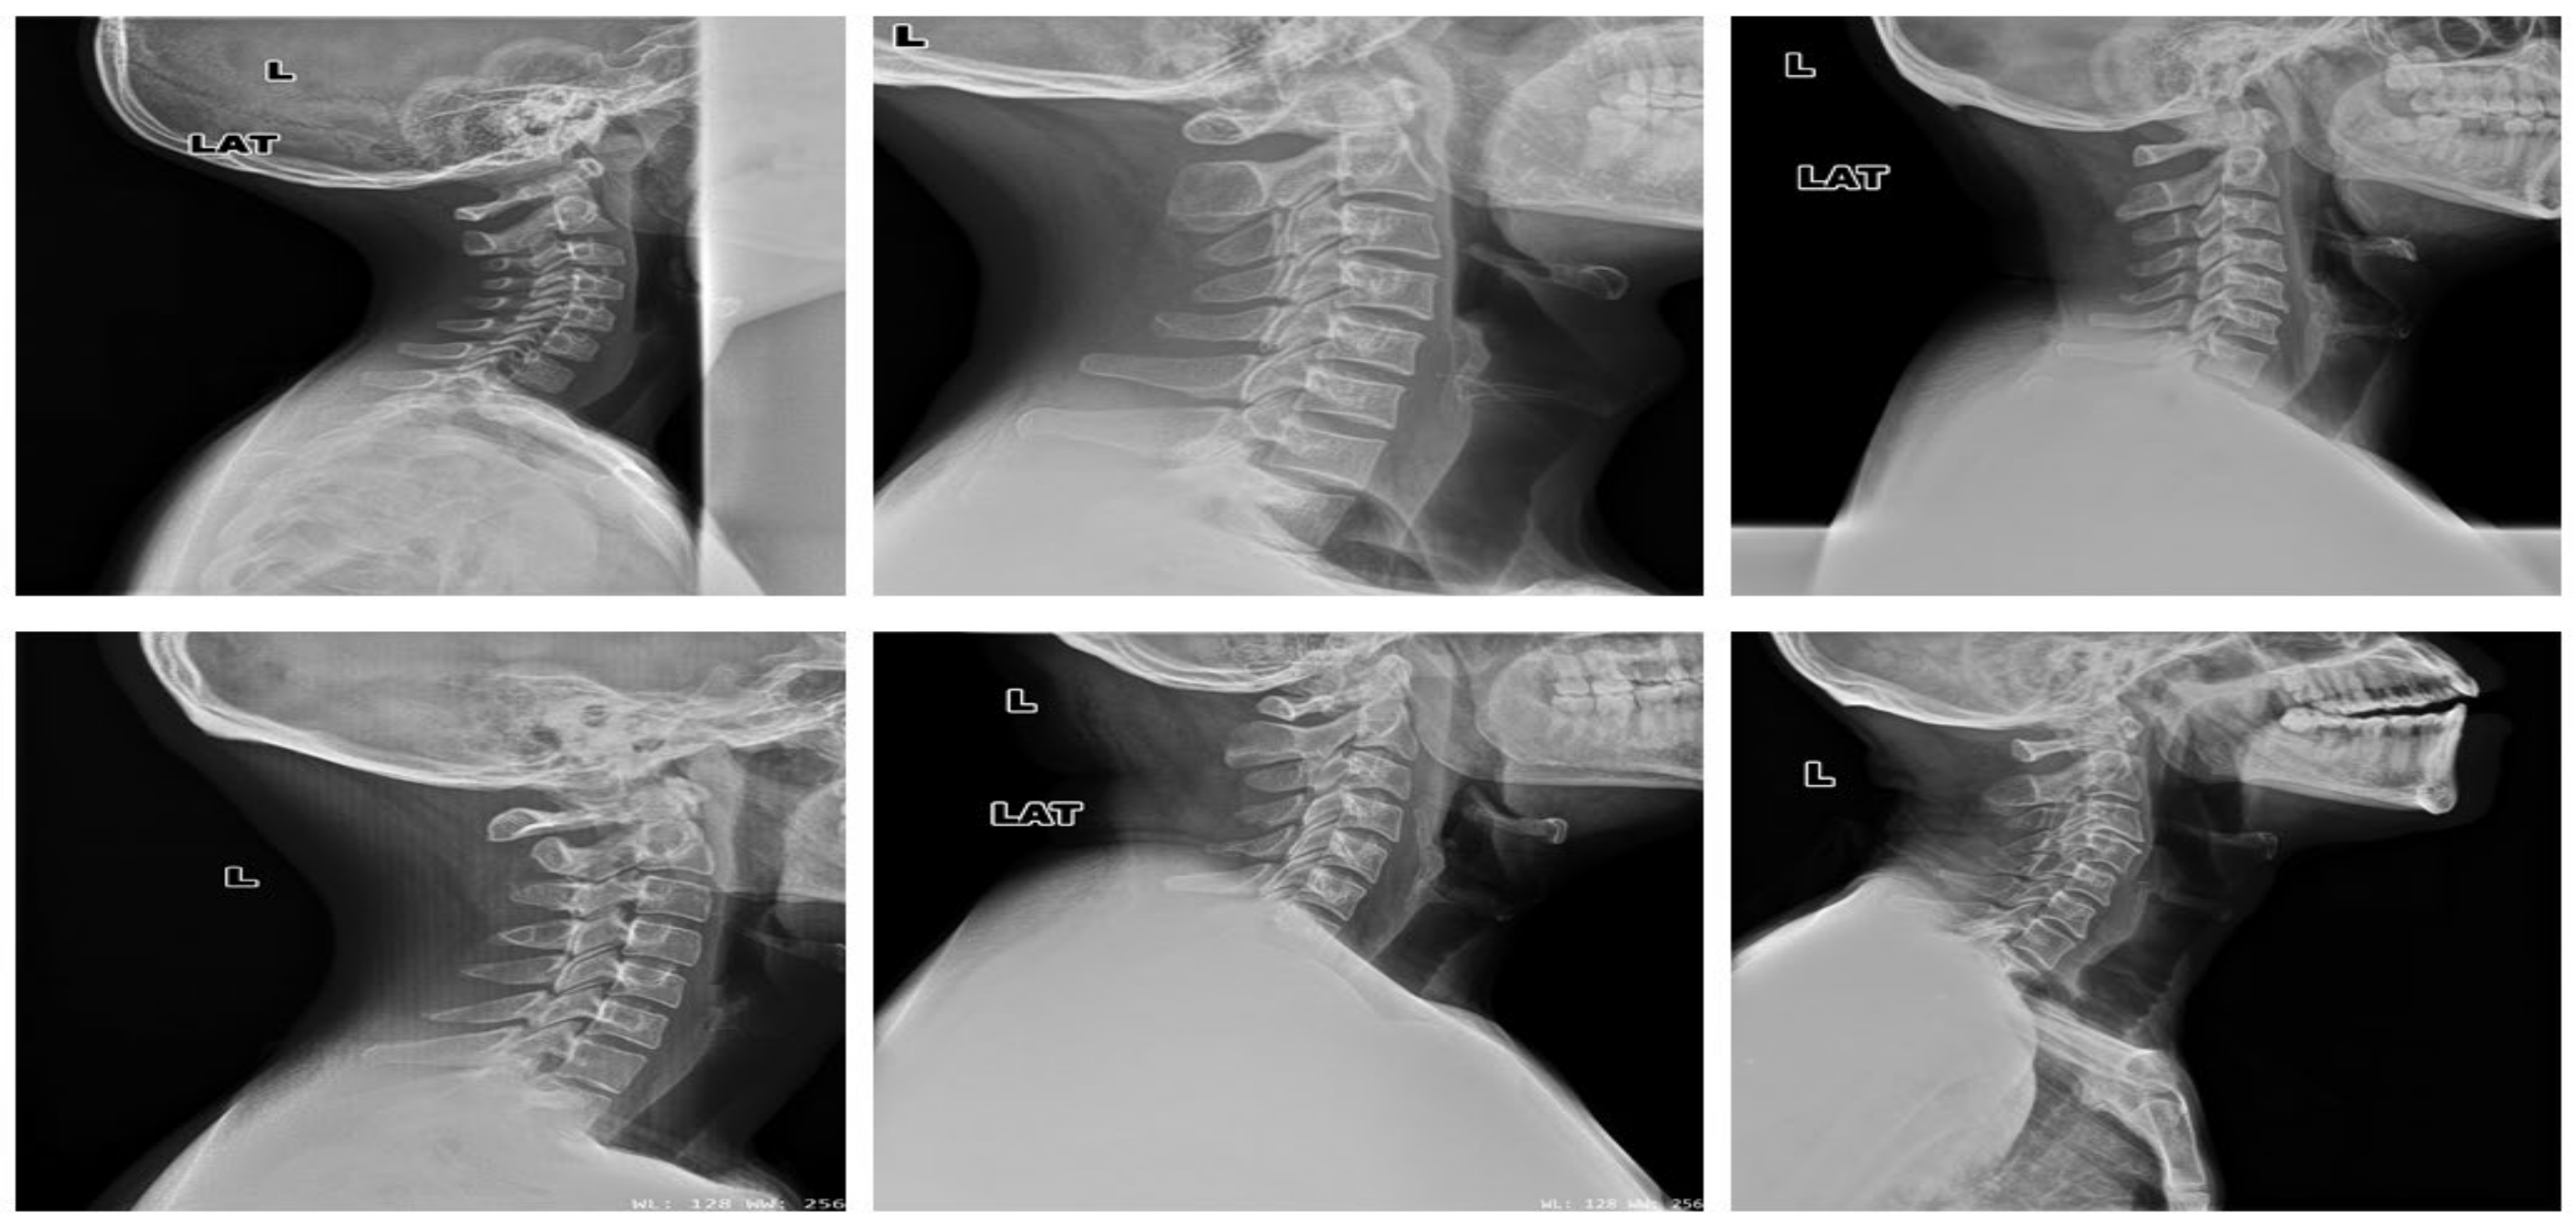

3.1. Datasets

4.1.2. Clinical Case Study